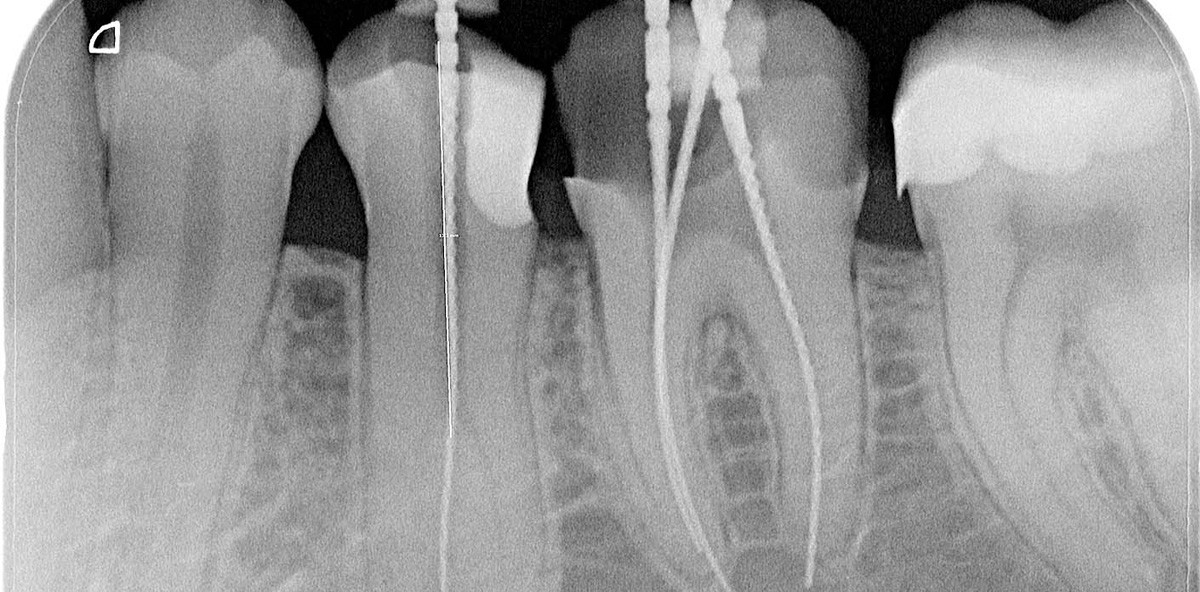

Der Patient war beschwerdefrei geblieben. So wurde der Zahn anästhesiert, unter Kofferdam isoliert und der provisorische Verschluss entfernt. Unter OPMI wurde vorsichtig mittels zu Trepanbohrern gekürzten Gates-Glidden-Bohrern (VDW) der koronale Kanalanteil erweitert, sodass der zweite bukkale Kanal sicht- und mit einem Micro-Opener ISO 10.02 (Dentsply Sirona) tastbar wurde. Anschließend wurde das koronale Pulpenkavum mit Ultraschallansätzen (ACTEON) und dem Ultraschallgenerator VDW.ULTRA (VDW) so weit nach bukkal erweitert, dass sich eine C-Pilot-Feile in ISO 10 ohne Vorbiegung in den Kanal einführen ließ. Nach endometrischer Längenbestimmung erfolgte die Röntgenmessaufnahme beider Kanäle (Abb. 2). Die Aufnahme zeigt zudem eine apikale Osteolyse, die bei Behandlungsbeginn vor vier Wochen noch nicht sichtbar war. Der bukkale Kanal wurde ebenfalls mit einer RECIPROC®-Feile R25 aufbereitet. Beide Kanäle wurden mit dem bekannten Spülprotokoll desinfiziert, mit AH Temp als medikamentöse Einlage versorgt und der Zahn mit Komposit verschlossen.

Der Patient stellte sich nach erneuten vier Wochen beschwerdefrei zur Wurzelfüllung vor. Nach lokaler Anästhesie, Isolierung unter Kofferdam, Entfernung der provisorischen Füllung und Desinfektion mit dem bekannten Spülprotokoll wurden nach erneuter endometrischer Überprüfung der Arbeitslänge die Mastercones aus niedrigschmelzendem Guttapercha mit Taper 0.4 (VDW) eingebracht und röntgenologisch kontrolliert (Abb. 3). Die apikale Osteolyse zeigte sich gegenüber der Rötgenaufnahme vier Wochen zuvor unverändert. Die Wurzelfüllung wurde mit dem BeeFill 2in1 (VDW) in vertikaler Kompaktation durchgeführt (Abb. 4). Der linguale Kanal zeigt zudem einen weiteren, im Übergang zwischen mittlerem und apikalem Wurzelkanalabschnitt befindlichen late­ralen Kanalausgang. Es erfolgte der Verschluss des Zahnes mit Komposit. Ein drei Monate später angefertigter Zahnfilm (Abb. 5) zeigte eine deutliche Verkleinerung der apikalen Läsion.